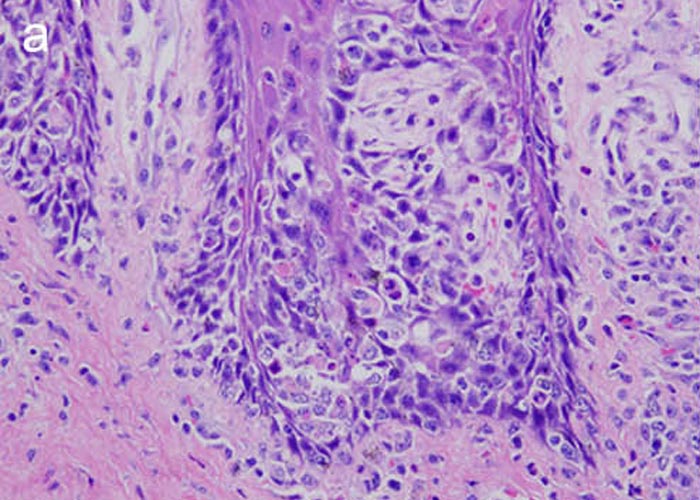

Histopathological lesions correspond to gross findings. Apoptosis of epithelial cells, particularly in suprabasilar stratified squamous epithelium, results in characteristic microvesiculation. This is seen in mucosa of the oral cavity, pharynx, larynx, oesophagus, forestomach and skin. While not unique to MCF, only a handful of infectious diseases in cattle and bison cause widespread microvesiculation, erosion and ulceration in epithelial mucosa and skin. Ulcerative enteritis and typhlocolitis are generally present. Urothelium appears to be a particular target of the dysregulated immune response of MCF. Degeneration, apoptosis and loss of urothelium in the renal pelvis, ureters, bladder and urethra is consistent, accompanied by lymphocytic-histiocytic inflammation (Figure 31).

Vascular lesions involve multiple organ systems, affecting arteries and veins. Veterinary pathology texts often illustrate the arteritis of MCF, since the thick lesioned walls of muscular arteries lend themselves to striking images. But phlebitis is equally widespread, albeit harder to identify.23 A pathologist who finds disseminated arteritis-phlebitis in tissues of cattle (Figure 32), bison and deer should consider MCF as a differential diagnosis. Examining the carotid rete (a rich vascular plexus surrounding the pituitary gland) (Figures 33 and 34), pampiniform plexus (intact males only) and/or vessels in the mesenteric stalk provides many appropriate-calibre veins and arteries for microscopic evaluation. Bison and deer tend to die of MCF after a shorter clinical course than cattle. This may explain why necrotizing medial arteritis, a useful hallmark of MCF in cattle, is less evident in those species.145,146,191,192 Deer with MCF sometimes have occlusive thrombosis with infarctions, a feature that is uncommon in bison and cattle.149

Lymphoid hyperplasia is generalized in lymph nodes of cattle, bison and cervid species that die of acute MCF. Some lymphocytes are large with lymphoblastoid features, but in more autolytic carcasses these can be hard to distinguish from reactive histiocytes. Similar lymphoblastoid cells are widespread in the inflammatory reaction of MCF, particularly in and around blood vessels. In lymph nodes they expand T-cell dependant areas. Multifocal degeneration of lymphocytes resulting in necrosis and oedema is common in lymph nodes, particularly in some cervid species. The inflammatory reaction of MCF around vessels is dominated by the presence of slightly atypical lymphocytes resembling or indistinguishable from macrophages. The typical infiltrate comprises lymphocytes, histiocytes-macrophages, plasmacytes, and neutrophils.

Disease due to CpHV-2 in sika deer can be associated with severe alopecic clinical dermatitis. In addition to necrotizing lymphocytic vasculitis, cutaneous lesions may be florid and granulomatous, with giant cell infiltration and mural folliculitis.35 Generalized vasculitis in non-cutaneous tissues may be granulomatous, although this is not invariable. It is unclear whether the chronic lesions associated with prolonged survival that are associated with CpHV-2 in some cervids reflect inherently lower viral pathogenicity relative to OvHV-2 or AlHV-1, or is a peculiarity of sika deer. OvHV-2 in experimentally-challenged rabbits causes a granulomatous response, generally within three weeks of challenge, most commonly in portal areas of the liver and, in some, is associated with widespread hepatic necrosis (Figures 35 a and b).